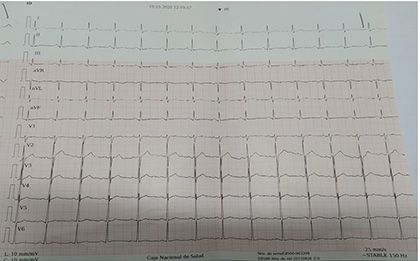

Cuatro meses después del cuadro inicial, el paciente fue hospitalizado nuevamente por cuadro de 4 horas de evolución caracterizado por presentar parálisis flácida de miembros superiores e inferiores, acompañado por parestesias en miembros inferiores, mialgias y disnea, sin alteración de funciones superiores, al examen físico con presión arterial 110/70, frecuencia cardíaca 90 latidos por minuto, tiroides de tamaño normal, sin alteraciones cardiopulmonares, sin temblor distal en manos. Entre los estudios de laboratorios realizados en emergencias destacó la presencia de hipopotasemia severa de 2,0 mEq/l. Con la sospecha de PPHT, se solicitó estudios de función tiroidea con resultados de TSH 0,01 uUI/ml (rango de referencia 0,4 y 4,5), T4 libre 3,09 ng/dl (rango de referencia 0,8 y 1,65), anticuerpos anti TPO 552 UI/ml (rango de referencia 0 a 95) y anti tiroglobulina 211 UI/ml (rango de referencia 0 a 30), tiroglobulina 17 ng/ml (rango de referencia 0 a 55), ecografía tiroidea que reportó de tamaño y morfología normal, sin evidencia de lesiones nodulares (Figura 1), electrocardiograma sin alteraciones (Figura 2). Se inició tratamiento con fármacos antitiroideos y betabloqueadores, además de jarabe de potasio, el mismo que se disminuyó de forma gradual hasta su suspensión. Hasta la fecha el paciente mantiene tratamiento con tiamazol 20 mg por día, con control adecuado de la función tiroidea, sin nuevos episodios de debilidad y/o hipopotasemia. Se presenta la evolución de la concentración de potasio sérico en la Figura 3.